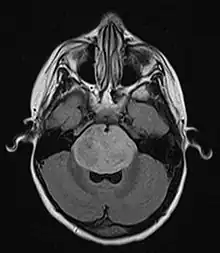

Brain stem glioma. MRI axial, with contrast

Neuroimaging, such as MRI, is the main diagnostic tool for brain stem gliomas. In very rare cases, surgery and biopsy are performed.